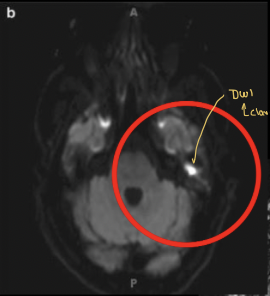

Q

Enfermedad que con la secuencia en T2 tipo DWi se muesta una lesión hipertensa

Diagnóstico probable

Qué estudio diagnostica el colesteatoma y cuál es la mejor pista

A

TC Y RM

Pista: Masa que destruye el hueso